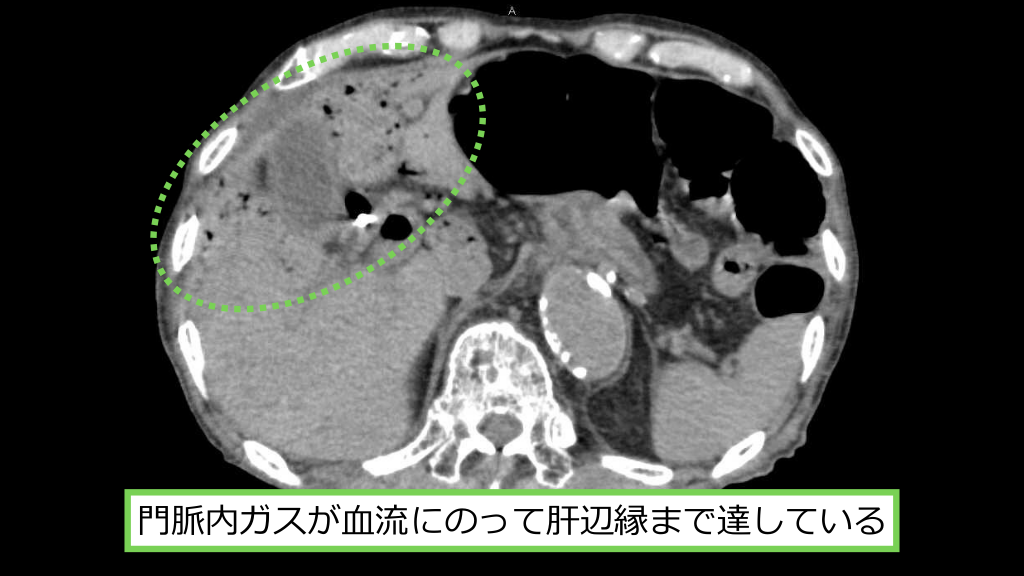

SMV ⾨脈 左腎静脈 壊死した腸管からSMV、⾨脈、左腎静脈へガスが迷⼊している

⾨脈内ガスが⾎流にのって肝辺縁まで達している